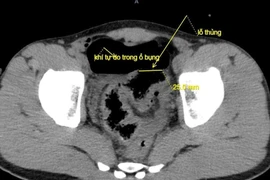

Bệnh viện Đa khoa tỉnh Lạng Sơn vừa cấp cứu thành công một trường hợp thủng đại tràng do bị bạn dùng vòi rửa xe ô tô áp lực cao xịt vào hậu môn.